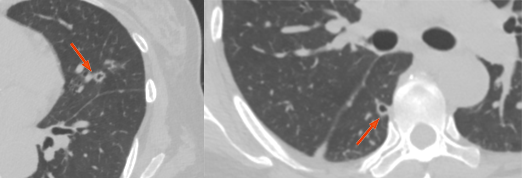

支气管内膜转移

CT 示支气管内息肉样肿物,支气管壁增厚,管腔狭窄,可形成黏液栓、合并阻塞性肺炎或肺不张。其发生机制可能是肿瘤细胞通过淋巴或血行直接播散转移至支气管壁、淋巴结或肺实质内,肿瘤细胞沿支气管树生长并突破支气管壁形成腔内病灶。

图片

两图分别为直肠癌支气管内膜转移、软骨肉瘤支气管内膜转移。